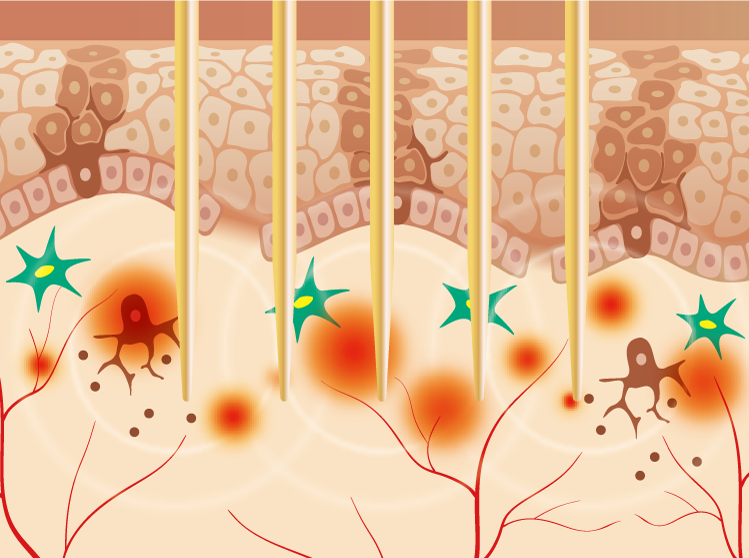

シルファームXは、世界初で唯一のデュアルウェーブ(連続波とパルス波)システムを搭載した低侵襲のマイクロニードルRF(高周波)です。非常に細い針で微小な損傷を作りRFエネルギーの熱効果を皮膚の奥深くまで伝達して、創傷治癒とコラーゲン生成を促進します。連続波モードでは真皮深層から表皮上層まで凝固して肌を再構築し、引きしめ、毛穴や小じわ改善、トーンアップなどの肌の若返りを実現させます。パルス波モードでは、基底膜や真皮上層に凝固をもたらし、老化した線維芽細胞や異常な毛細血管に作用して、従来のマイクロニードルRFで は困難だった肝斑や赤ら顔の治療を可能にしました。肌を土台から立て直していくことは、現在の症状を改善するのみならず、今後行うほかの治療の安全性および効果を高めることへ繋がりますので、どんな方へもおすすめしたい治療です。針が細く、かつ皮膚にやさしく挿入される設計のため痛みが少なく、24時間後からメイクが可能でダウンタイムが最小限です。当院では、画一的な照射方法ではなく、目的や症状に合わせてモードや設定を医師がカスタマイズして丁寧に照射します。また、チップ(マイクロニードル)は安全面や効果の観点から1回の治療で使い切りですので、ご希望があれば、顔以外にも首や頭皮、手背など広範囲に照射します。シルファームXは米国FDAおよび欧州CEで認証されています。

は困難だった肝斑や赤ら顔の治療を可能にしました。肌を土台から立て直していくことは、現在の症状を改善するのみならず、今後行うほかの治療の安全性および効果を高めることへ繋がりますので、どんな方へもおすすめしたい治療です。針が細く、かつ皮膚にやさしく挿入される設計のため痛みが少なく、24時間後からメイクが可能でダウンタイムが最小限です。当院では、画一的な照射方法ではなく、目的や症状に合わせてモードや設定を医師がカスタマイズして丁寧に照射します。また、チップ(マイクロニードル)は安全面や効果の観点から1回の治療で使い切りですので、ご希望があれば、顔以外にも首や頭皮、手背など広範囲に照射します。シルファームXは米国FDAおよび欧州CEで認証されています。